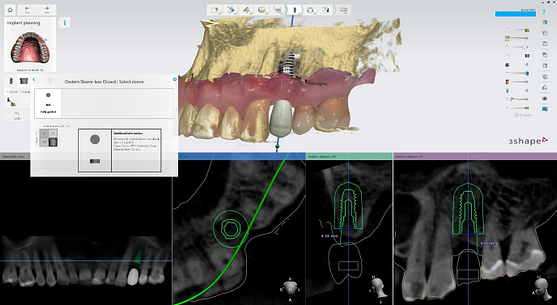

I utilized 3Shape Implant Studio, a module within the 3shape Unite Platform, to plan and execute the surgical procedure.

Pre-surgical planning began with acquiring high-quality diagnostic data, including TRIOS intraoral scans and CBCT imaging. The data was imported into 3Shape Implant Studio, where I designed a virtual crown for tooth 24 and planned the precise positioning of the implant, considering critical factors such as sinus proximity, adjacent roots, bone density, and the location of the bony defect.

A custom surgical guide was designed and 3D printed, incorporating all the critical information from the virtual planning. The implant surgery was performed under local anesthesia, with the surgical guide firmly in place to ensure accurate implant placement. Bone grafting was performed to address the bony defect and promote optimal healing.

The Osstem OneGuide kit is used with a fully guided osteotomy and implant placement.

Osstem TSIII D4 x H10mm implant on NoMount driver.